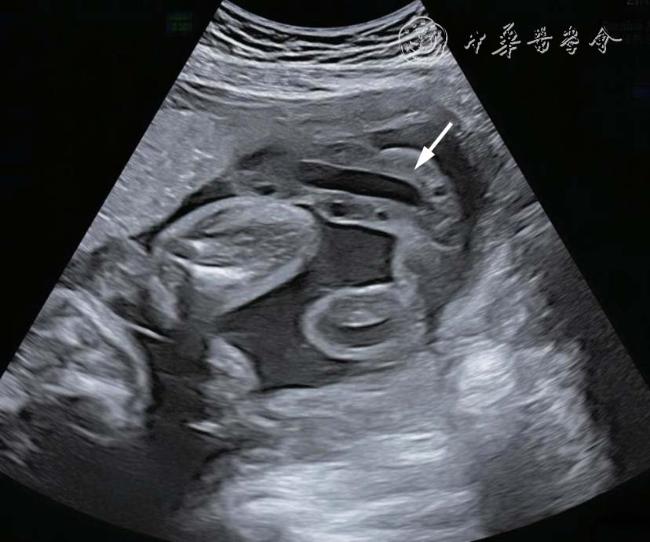

26 例TAPS 均在中晚孕期(孕17+1~34+6 周)超声检查中发现,其中Ⅰ期11 例,Ⅱ期3 例,Ⅲ期3 例,Ⅳ期9 例,Ⅴ期0 例。共有的超声特征为:(1)供血儿MCA-PSV 增高(>1.5 MoM),受血儿MCA-PSV 降低(<1.0 MoM)( 图1);(2)“黑白”胎盘:供血儿脐带入口附近胎盘回声增强、增厚,受血儿脐带入口附近胎盘回声减低、较供血儿侧薄(图2)。其他超声特征包括:(1)24例(92%)受血儿肝呈“星空征”(图3);(2)4例(15%)供血儿肠管回声增强(图4);(3)22例(85%)心脏异常,包括心胸比增大、房室瓣反流、房室瓣频谱呈单峰、心肌增厚等征象(图5a、5b);(4)18 例(69%)多普勒血流异常,包括脐动脉、脐静脉、静脉导管A 波异常等;(5)9 例(34%)胎儿水肿,包括皮肤水肿、胸腹腔积液、心包积液;(6)15 例(57%)羊水量不均衡;(7)19 例(73%)脐带异常,包括脐带水肿、脐带插入点异常(图6);(8)15 例(57%)合并双胎选择性宫内生长受限(selective intrauterine growth restriction,sIUGR)、TTTS(表1)。对供血儿及受血儿其他超声特征进行统计分析发现,受血儿肝“星空征”、脐带水肿,供血儿肠道回声增强、胎儿水肿、心胸比增大特征比较,差异有统计学意义(P<0.05,表2)。

图1 双胎贫血-红细胞增多序列征胎儿孕29+1周产前超声图像。图a:供血儿大脑中动脉峰值流速(MCA-PSV)增高,约1.61 中位数倍数(MoM);图b:受血儿MCA-PSV 降低,约0.87 MoM